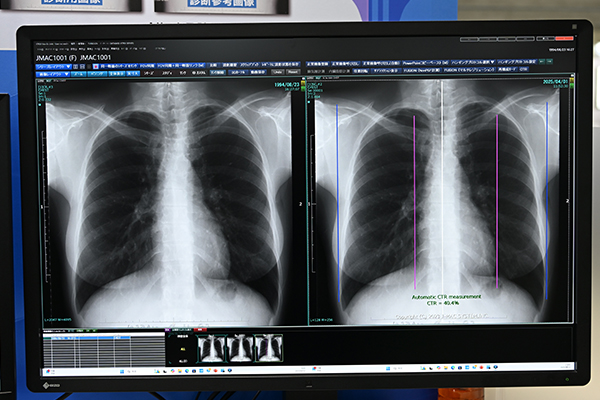

ジェイマックシステムでは,AIの開発を進めており,前回のITEMでも技術展示として開発中の機能を紹介してきた。今回はAIブランドとしてRely-AIを商標登録して,本格的に展開していくことをアナウンスした。Rely-AIの第一弾として発表したのが,肋骨減弱機能と心胸郭比計測機能である。両機能とも薬機法の承認を得ており,今後正式に上市する予定である。肋骨減弱機能は,胸部X線画像から肋骨を減弱処理して,視認性を向上。結節などを検出しやすくする。また,心胸郭比自動計測機能は,胸部X線画像から胸郭を自動で計測することで高精度かつ効率的な診断を支援する。病院をはじめ,健診センターなどの検診施設のように胸部X線撮影の検査数が多い施設,呼吸器科をターゲットに展開していくこととしている。

高精度で効率的な診断を支援する「心胸郭比計測機能」